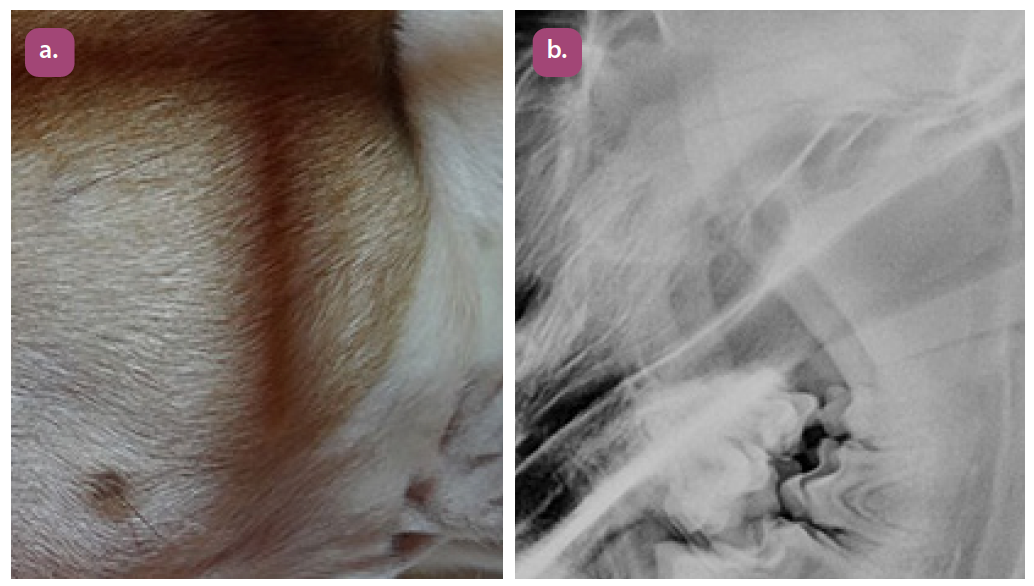

lateral oblique temporomandibular joint projection